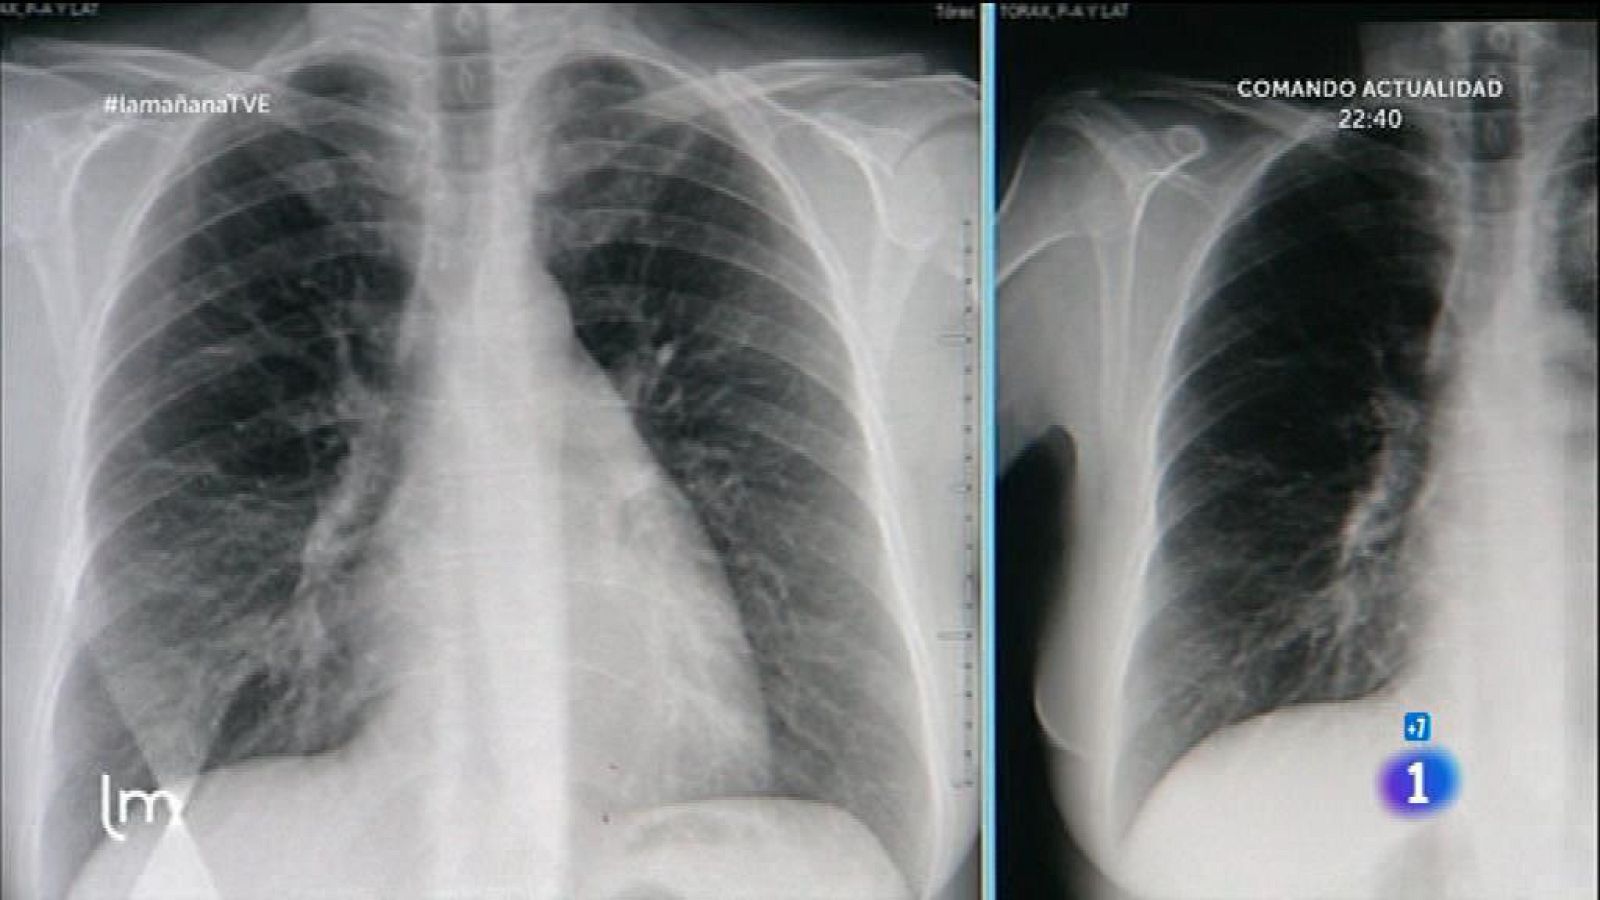

Problemas respiratorios